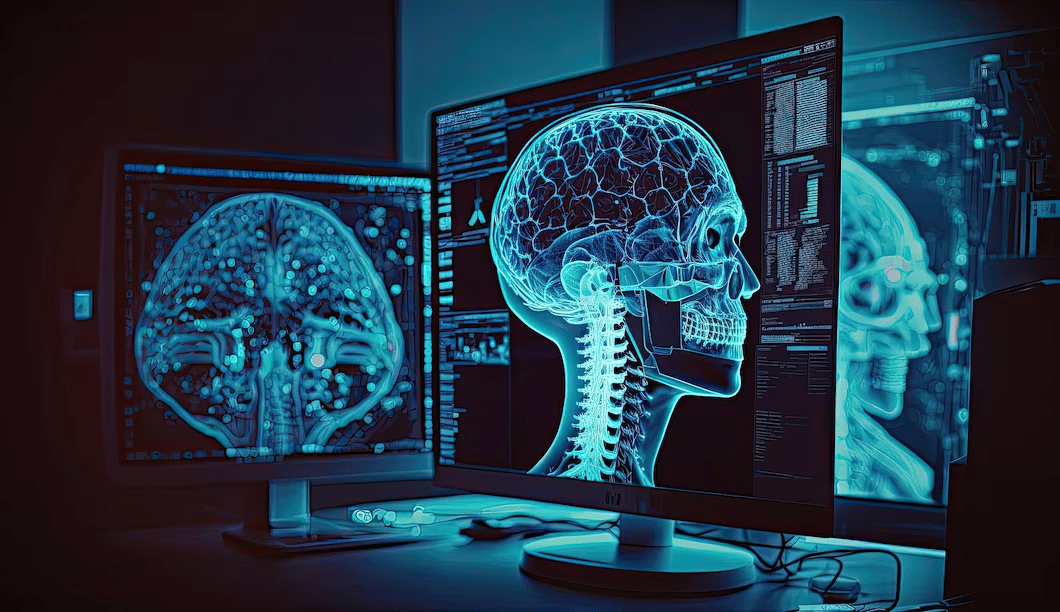

A Review of the Historical Development and Future Significance of Artificial Intelligence in Radiology

The discipline of radiology has a long and significant history that traces back to 1895 when Wilhelm Röntgen made the...Read More